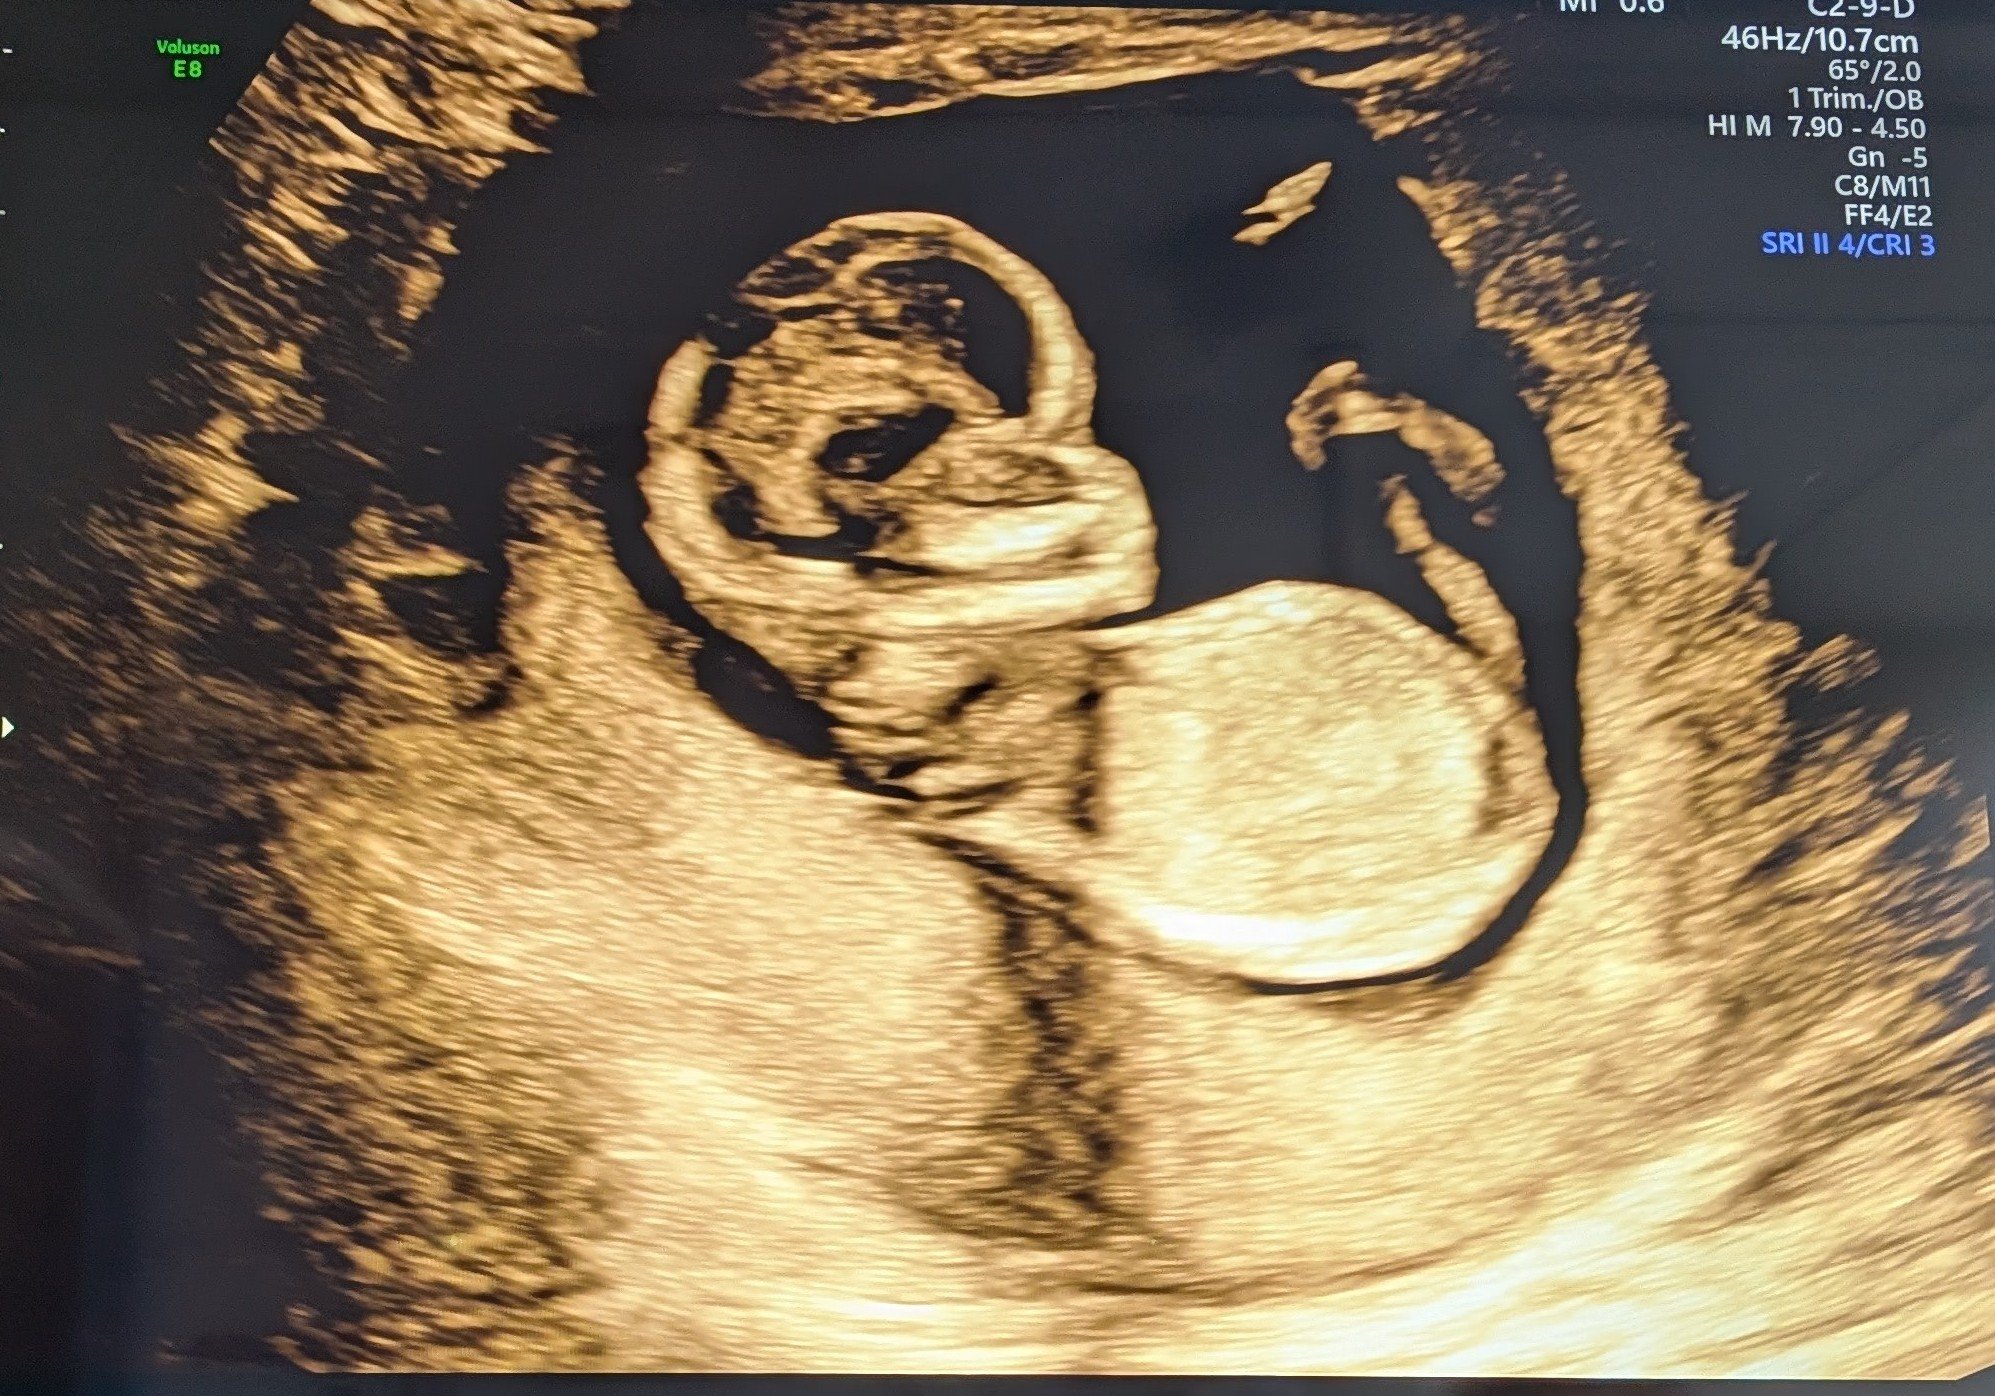

Mannen tenkte feil (selv om han sa kl høyt) og vi endte opp på sykehuset 1 t før OTUL. Utforsket bygget imens. Plutselig fikk jeg sms om at det var min tur! :oops: Viste seg at hun som hadde timen før meg satt fast i kø, så da fikk jeg hennes. Flaks da! Rakk såvidt å bli nervøs. Pratet litt før timen, om forrige fødsel og evt. oppfølging nå, får vite mer om det på OUL. Før vi begynte var hun veldig klar på at man ikke får vite kjønn. Vi sa det går heelt fint, vi er ikke opptatt av det. Jeg syns egentlig folk er litt for opptatt av kjønn :bag: Det syns hun var forfriskende! Også sa hun "eg seie alltid han pga. dialekt". Vi snakket litt videre om datteren vår ila. timen, og etterhvert begynner hun å si "ho" - hun skyldte fort på at det var pga. vi har jente fra før, men lurer på om hun forsnakket seg der :p Anyway, vi så med én gang at det var en frisk og superaktiv krabat inni der! Den hoppet og turnet og snurret rundt - med boksenever foran ansiktet :laughing002 Skulle ikke drukket de slurkene med red bull, for det var vanskelig å få målt :smiley-ashamed004 Men det gikk etterhvert, fikk akkurat nakkefolden til slutt. Ble mange bilder også, inkl. i 3D! Alt så veldig bra ut. Så ingen nub, men jeg kan ikke de greiene uansett. Men basert på at jeg ikke så en penis og en potensiell forsnakkelse lurer jeg på om det blir ei jente til :joyful: Jeg hadde jo egentlig lyst på gutt, men kjenner ikke på noen skuffelse der, selv om det ikke er sikkert ennå. Holder forresten mistanken min privat, for kjente jeg ble litt irritert at alle drev og spurte etter kjønnet etter jeg snappet om vellykket UL :rolleyes: Det er ikke viktig! Senere gikk jeg forbi en Brando Kids og fant ei kasse med ull til 50%, så kjøpte noen plagg i 50-56 :D Det var for det meste "jentefarger" men det driter jeg i :wacky: Fikk btw OUL den 17.09. (18+2)!